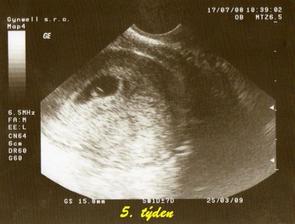

tak tohle album obsahuje vše co se týká našeho prvního miminka, které nosím pod svým srdíčkem, výbavičky co chystáme a co bychom chtěly nachystat.. Narodit se má 6.3.2009 , nevíme co to bude - asi necháme jako překvapení.